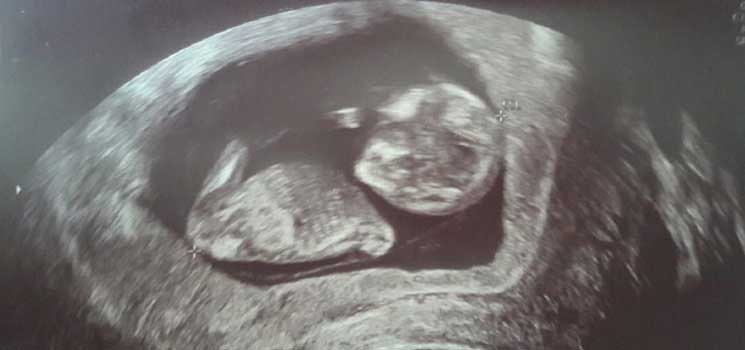

Die erste Vorsorgeuntersuchung - Tagebücher aus der Schwangerschaft von Leandra aus Lübeck